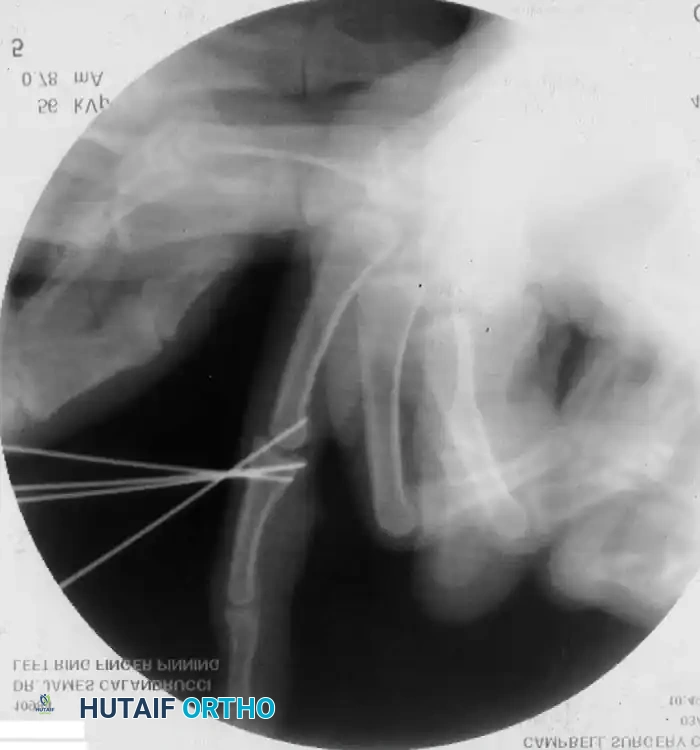

4. Chronic Instability: Autogenous Hemihamate Osteoarticular Grafting

When PIP joint dorsal subluxation persists even with 30 degrees of PIP joint flexion, or when >50% of the volar lip is destroyed and cannot be fixed, an autogenous hemihamate osteoarticular graft is recommended (Williams et al.).

A size-matched segment of the distal hamate articular surface (between the 4th and 5th metacarpal facets) is harvested. This graft perfectly matches the bicondylar contour of the middle phalanx base.

Surgical Pearl: Despite the dramatic stability achieved intraoperatively with a hemihamate graft, it is highly recommended to protect the repair with provisional transarticular K-wire pinning for 2 weeks to prevent graft displacement during early healing.